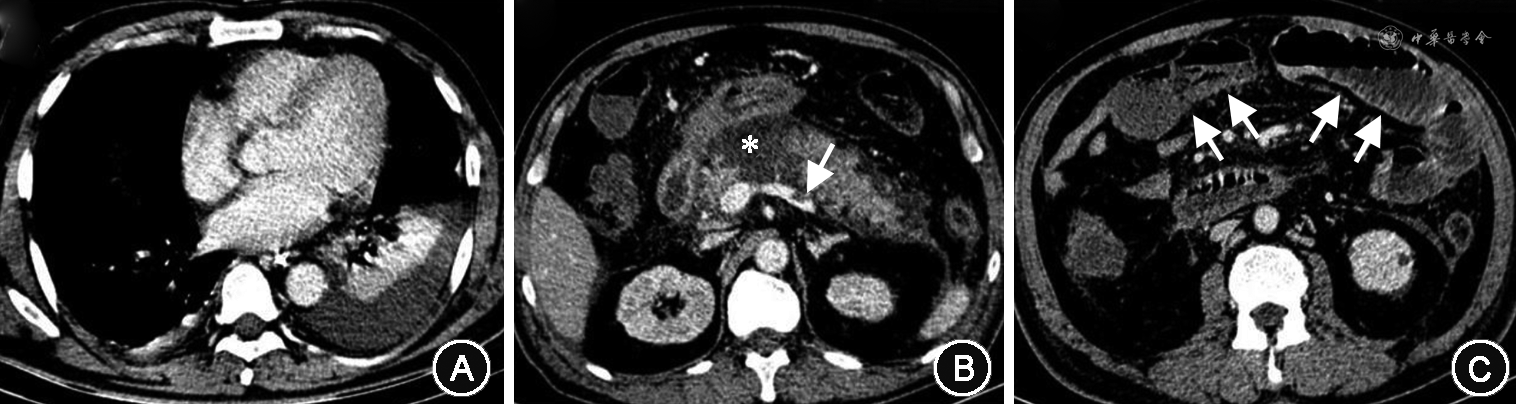

AP病因分类标准参照相关指南[7, 8];RAC标准下的AP严重度分级,是在具有自动评分和自动诊断功能的AP数据库根据收集的资料自动判定为MAP、MSAP和SAP[6]。胰腺的形态改变、局部并发症和胰腺外并发症由两名具有10年工作经验以上的影像科医师在不知临床资料的情况下分别评估,评估结果不一致经协商判定;评估结果录入AP数据库后由系统自动计算CTSI和MCTSI评分(表1)。根据CTSI得分将AP严重程度分3级[6]:MAP 0~3分;MSAP 4~6分;SAP 7~10分。同样以MCTSI得分评估AP严重程度[6]:MAP 0~2分;MSAP 4~6分;SAP 8~10分(图1)。坏死性胰腺炎的诊断标准:CT增强检查胰腺内出现无强化区域和(或)胰周积液密度混杂、见脂肪碎片(脂泡影)[9]。IPN的诊断标准[5]:CT显示胰腺和(或)胰周坏死组织内出现气体;或胰腺坏死细针抽吸行细菌涂片或培养检出细菌或真菌。器官衰竭和持续性器官衰竭的诊断采用改良的Marshall标准[5]。纳入的AP患者均参考国内外指南及共识给予规范的综合治疗[5,7, 8,10],治疗原则包括早期液体复苏和镇痛;器官衰竭者给予重症监护和器官支持治疗;MAP经口进食低脂食物,不能耐受经口饮食的MSAP及SAP给予肠内营养;腹胀者应采取胃肠减压,口服生大黄或乳果糖口服液促进排便;病情稳定的IPN患者给予抗生素抗感染,治疗1周无效,给予升阶梯微创治疗,微创治疗病情无改善者考虑手术。